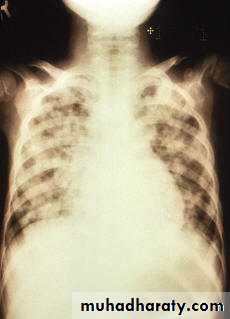

Chickenpox pulmonary x-ray

Varicella (Chickenpox)Bacterial superinfection

Varicella pneumonia